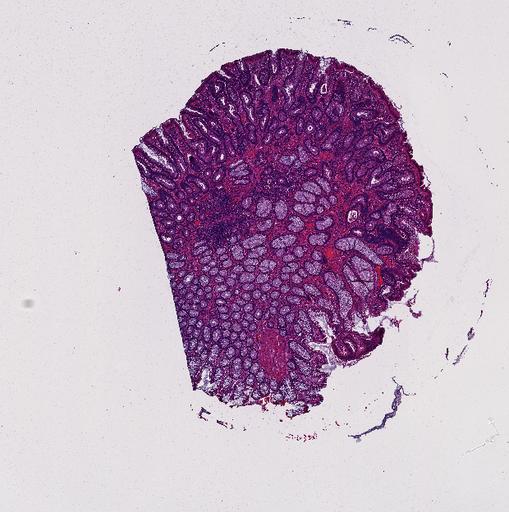

High‑resolution three‑dimensional (3D) tissue atlases promise to redefine how we study cellular architecture‑function relationships in human tissues. Large-scale consortia such as the Human Bimolecular Atlas Program (HuBMAP) systematically build detailed 3D organ maps by profiling serial tissue sections with single-cell spatial technologies. However, an accurate and efficient reconstruction method that can handle atlas-scale datasets remains elusive. We introduce Space-map, an open-source method that integrates single‑cell coordinates with optional histological image features to assemble serial sections into 3D models. Space‑map combines multi‑scale feature matching with large‑deformation diffeomorphic metric mapping, delivering global reconstructions while preserving local micro‑anatomy. To demonstrate the capability of Space-map, we generated a serially sectioned spatial transcriptomics (Xenium, ~2.9M cells) dataset and a spatial proteomics dataset (CODEX, ~2.4M cells). Applying Space-map to these single-cell spatial maps, we built three 3D models for both diseased (colon polyp) and reference colon tissues. These high-resolution 3D models showcase the intricate structure of the human colon across different states. Space-map is fast and highly efficient. We demonstrated its performance and accuracy using in‑house and public datasets. The result shows that Space‑map is 10 times faster and ~2‑fold more accurate than PASTE and STalign, making 3D atlas reconstruction more accessible. Our study provides a new robust and user-friendly software available at https://github.com/a12910/spacemap that can be easily applied for constructing molecular 3D tissue maps of human organs at single-cell resolution.